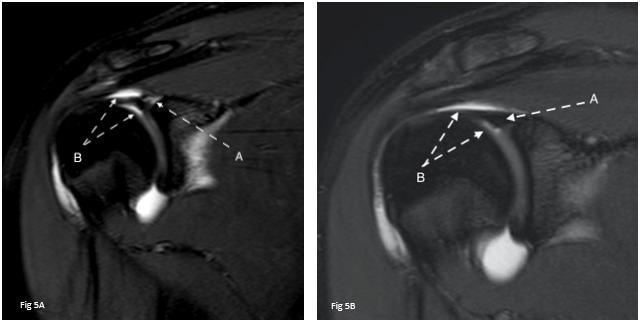

Interest is gaining in US’s ability to view muscles both statically and dynamically 34–40 Dynamic US protocols have been published by an international group of experts to help clinicians evaluate structures while recording video during real-time patient examination to improve their understanding of their diagnosis.41–44 Dynamic ultrasound allows for real-time visualization of structures as they move in relation to other structures. For example, the movement of adjacent fascial layers can be evaluated during active muscle contraction to assess fascial mobility. Muscle architecture can be examined under contraction or relaxation for deficits.